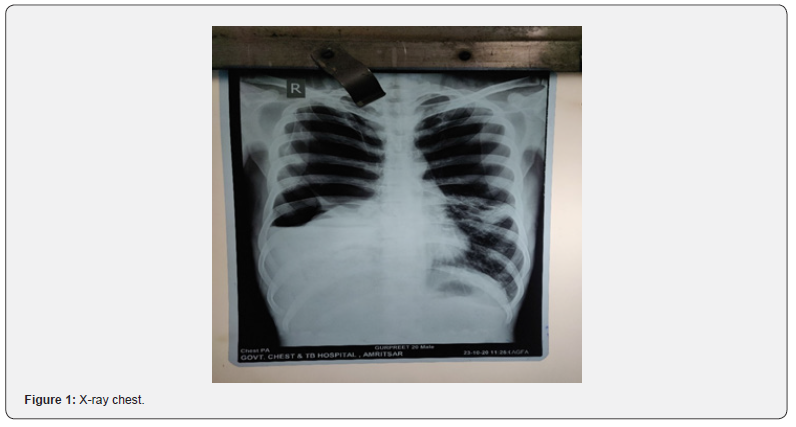

On laboratory investigation: hemoglobin: 9.2, total leucocyte Count: 14000 differential leucocyte count: 75, 22, 0, 3; Erythrocyte sedimentation rate: 42, liver function test and renal function test were within normal limits. HIV status was negative and anti-HCV was positive. The pleural fluid analysis showed an exudative picture with glucose 65gms, protein 3.5, and neutrophilic predominance. Gram stain culture sensitivity showed pseudomonas aeruginosa growth. Sputum for acid-fast bacilli and CBNAAT for Pulmonary TB showed a negative result. X-ray chest (Figure 1) showed right-sided hydropneumothorax, left-sided large hyperluscent area. Chest tube intubation was done in right 6th intercostal space.